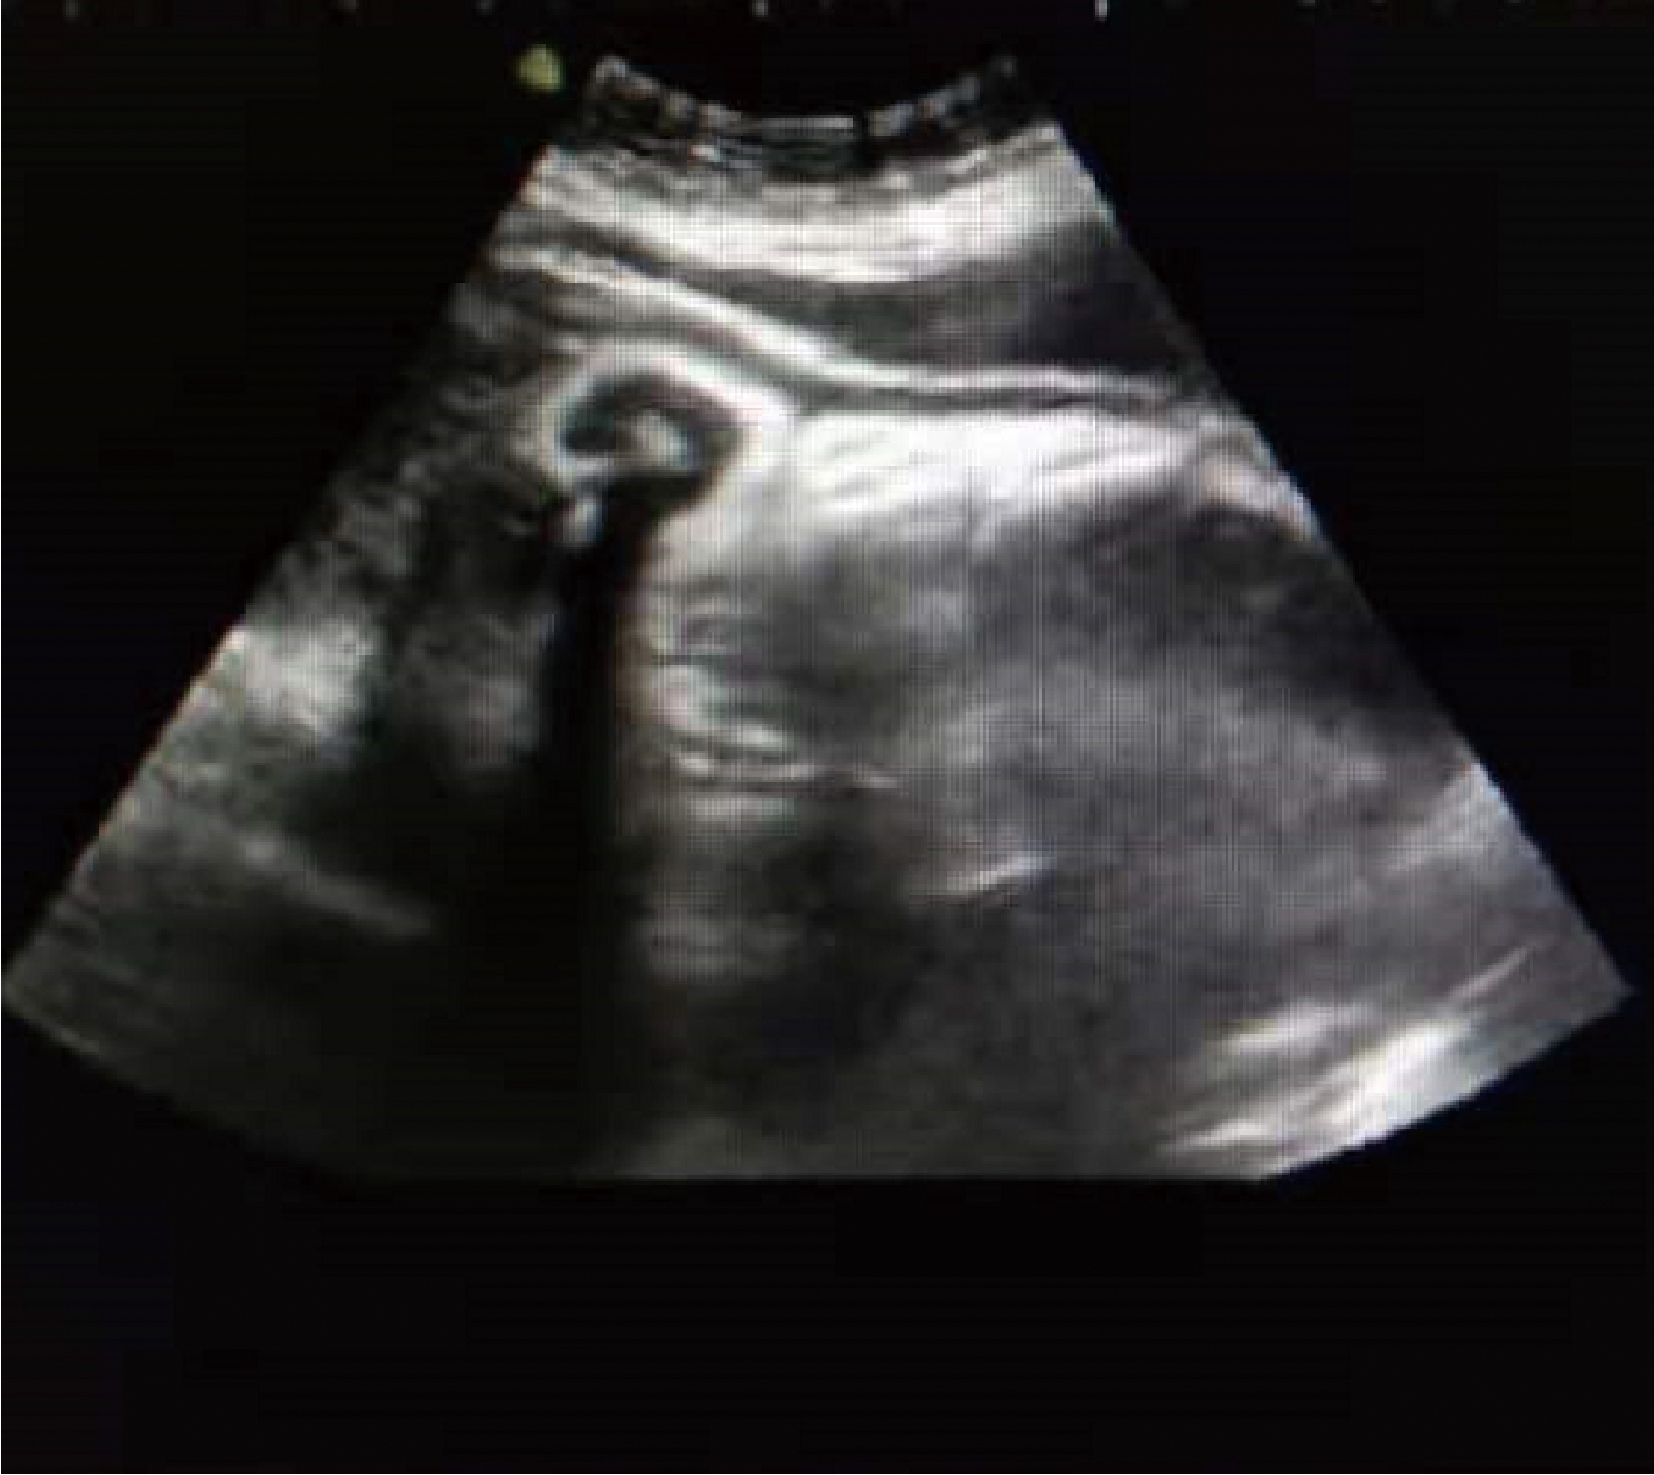

To improve clinicians' understanding, and to explore the diagnosis and treatment of pregnancy complicated with patent urachus. The clinical symptoms, ultrasound images, and delivery outcome of the pregnancy complicated with patent urachus were reported, and the literature was reviewed. The patient had umbilical leakage as a young child occasionally, the symptom of leakage was not obvious after she was 10 years old, and there was no asymptomatic before pregnancy and in the first and second trimesters. Umbilical leakage was present at gestational 33 weeks, and ultrasound showned a tubular structure (0.7 cm in width) was connected between the top of the bladder and the umbilicus, and there was anechoic areas inside. The pregnancy complicated with patent urachus was diagnosed. The patient was checked regularly, and kept the umbilicus clean and dry. Premature rupture of membranes occured at gestational 39 weeks 4 days. The patient was admitted to the obstetrics department, and she deliveried finally. After delivery, the symptoms of umbilical leakage urine relieved, and an elective resection of abnormal urachus was planned. The patent urachus creates a tube connection between the umbilicus and the anterosuperior wall of the bladder, it was termed an median umbilical ligament at birth as usual, which still communicated with the bladder after birth. The main clinical manifestations were umbilical leak and infection, which were the main diagnostic basis. Ultrasound, CT and MRI were important auxi-liary examination methods.The patients with symptoms in the neonatal and early childhood period were managed actively and had the potential for self resolution, especially for the children younger than 1 year. Therefore, patients under 1 year of age were offered surgery only if they had recurrent infections or failed to selfresolve. It is recommended to remove abnormal urachus before pregnancy for the women complica-ted with patent urachus. If the patent urachus was found during pregnancy, the umbilicus should be kept clean and dry to avoid infection. The pregnancy complicated with patient urachus is not contraindicated to vaginal delivery.

Figure 1

Pregnancy with patent urachus"